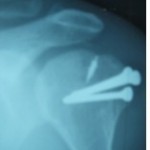

A 22-year-old previously healthy female came to hospital emergency room with multiple fractures following fall from height. She had closed femur shaft fracture (AO 32B2) and comminuted patella fracture on the left side (AO 34C3), type IIIA open femur shaft fracture on the right side (AO 32B2), and undisplaced mandible fracture (Fig. 1). A whole body computed tomography (CT) scan revealed no other injuries. She was planned for the early total care with definitive fixation since she was a borderline patient (ISS score 17). Before taking up for fixation, a repeat CT scan of brain was done at 8 h post-injury as she was noticed to have disconjugate eye movements and monosyllable speech. The repeat CT also showed no cerebral bleed. About 10 h post injury, she was taken to the operating room. She underwent debridement of the right thigh wound, bilateral femur antegrade nailing with minimal reaming and tension band wiring of the left patella fracture (Fig. 2). Surgery lasted for 5 h with no hypotension or hypoxia intraoperatively. She was ventilated overnight and on reassessing her on 1st post-operative day (POD), she was not responding to commands and not moving her limbs. Her Glasgow Coma Scale (GCS) was E1VTM1 and remained until POD5. Her chest X-ray and CT brain were normal. On POD 1, she had pyrexia, tachycardia, anemia, and thrombocytopenia. On POD 3, she developed features of decerebrate rigidity and later generalized tonic clonic seizures. Fundoscopic examination showed multiple fat globules along the vessel in the entire field of both eyes. Since there were no pulmonary or dermatological signs of FES, an MRI of brain was done which revealed hyper intensive starfield pattern on diffusion-weighted image, suggestive of FES (Fig. 3). Supportive treatment with antiepileptics, antibiotics, and anticoagulants was given.